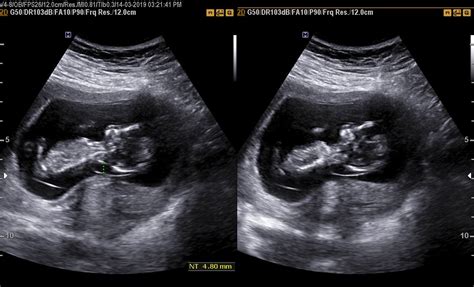

De regulă, medicii recomandă efectuarea unei ecografii transvaginale între săptămânile 11 și 13 + 6 zile. Această ecografie poate fi efectuată însă și transabdominal. În timpul primei ecografii, medicul va verifica dacă embrionul s-a implantat bine în uter, dacă nu se află în locuri improprii și va stabili numărul de embrioni prezenți. Această ecografie evaluează de asemenea și vârsta sarcinii și data concepției, făcând astfel posibilă evaluarea datei probabile a nașterii. De asemenea, în timpul acestei ecografii, se va evalua obligatoriu și translucența nucală, un test care îi permite medicului să descopere dacă fătul prezintă riscul de a avea sindromul Down sau alte boli cauzate de anomaliile cromozomiale.

Examinarea ecografică pentru screeningul anomaliilor din trimestrul I se efectuează între 11 și 13+6 săptămâni de amenoree (LCC / CRL între 45 și 84 mm), perioada optimă fiind la sfârșitul săptămânii a 12-a și începutul săptămânii a 13-a (când LCC / CRL este între 60 și 75 mm).